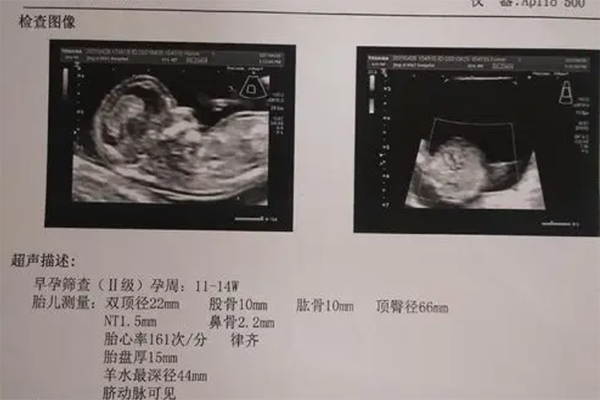

问题描述: 我目前怀孕13周,前段时间去医院做nt检查的时候,看到厚度显示为2.1mm,医生说这是正常的,让我不要担心。所以回到家后我就给妈妈说了,没想到妈妈却说nt值越小越好,还说这代表着生出来的小孩以后会越来越聪明,可是我并不是很相信这个说法,因此,就想来这里问问大家,真的代表越聪明吗?